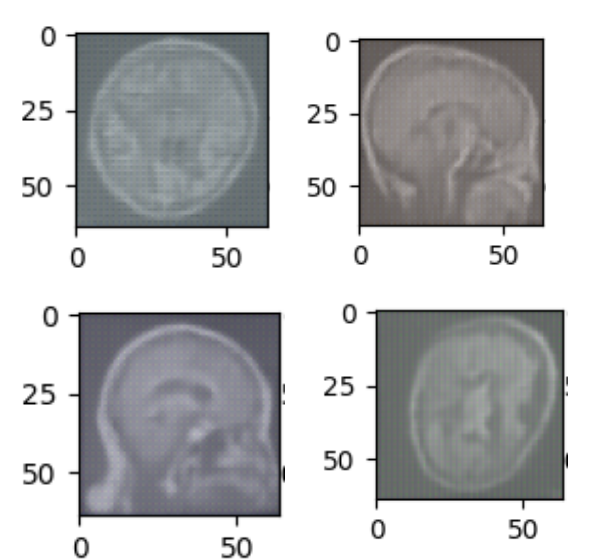

We trained a custom Diffusion model to generate images of medical conditions. We chose a MRI dataset just because it was the first one we saw. Otherwise we could in theory have used any other dataset. Which makes the model very adaptable. These generated images will be uploaded to the Streamlit web application at the press of a button. The user can practice determining what kind of tumor is shown in the generated image and their selection is confirmed using a classifier model that will also attempt to classify the generated image.

There was a big challenge we had. We at first decided to use 32x32 images to save computational power. This ended up in really pixelated and noisy images. This might have been due to the low batch size which restricted the models loss. We increased the image size and batch size and the model performed much better. Another challenge we ran into was creating and uploading the data to the ViT model. The data from the dataset has to be processed using transformers, but getting this to work was a problem as we ran into many authentication errors while trying to upload the dataset. Another problem we ran into was generating the image onto the Streamlit web app and attempting to classify it.